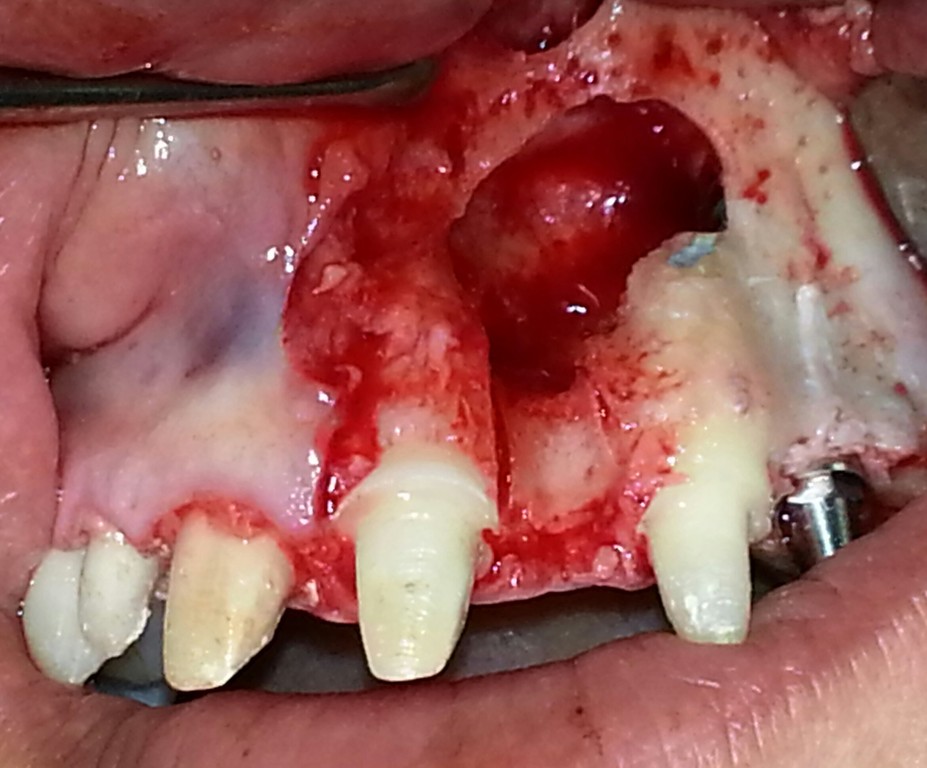

• EXTRACCIÓN DE CANINOS RETENIDOS.

EXTRACCIÓN DE CANINOS RETENIDOS.